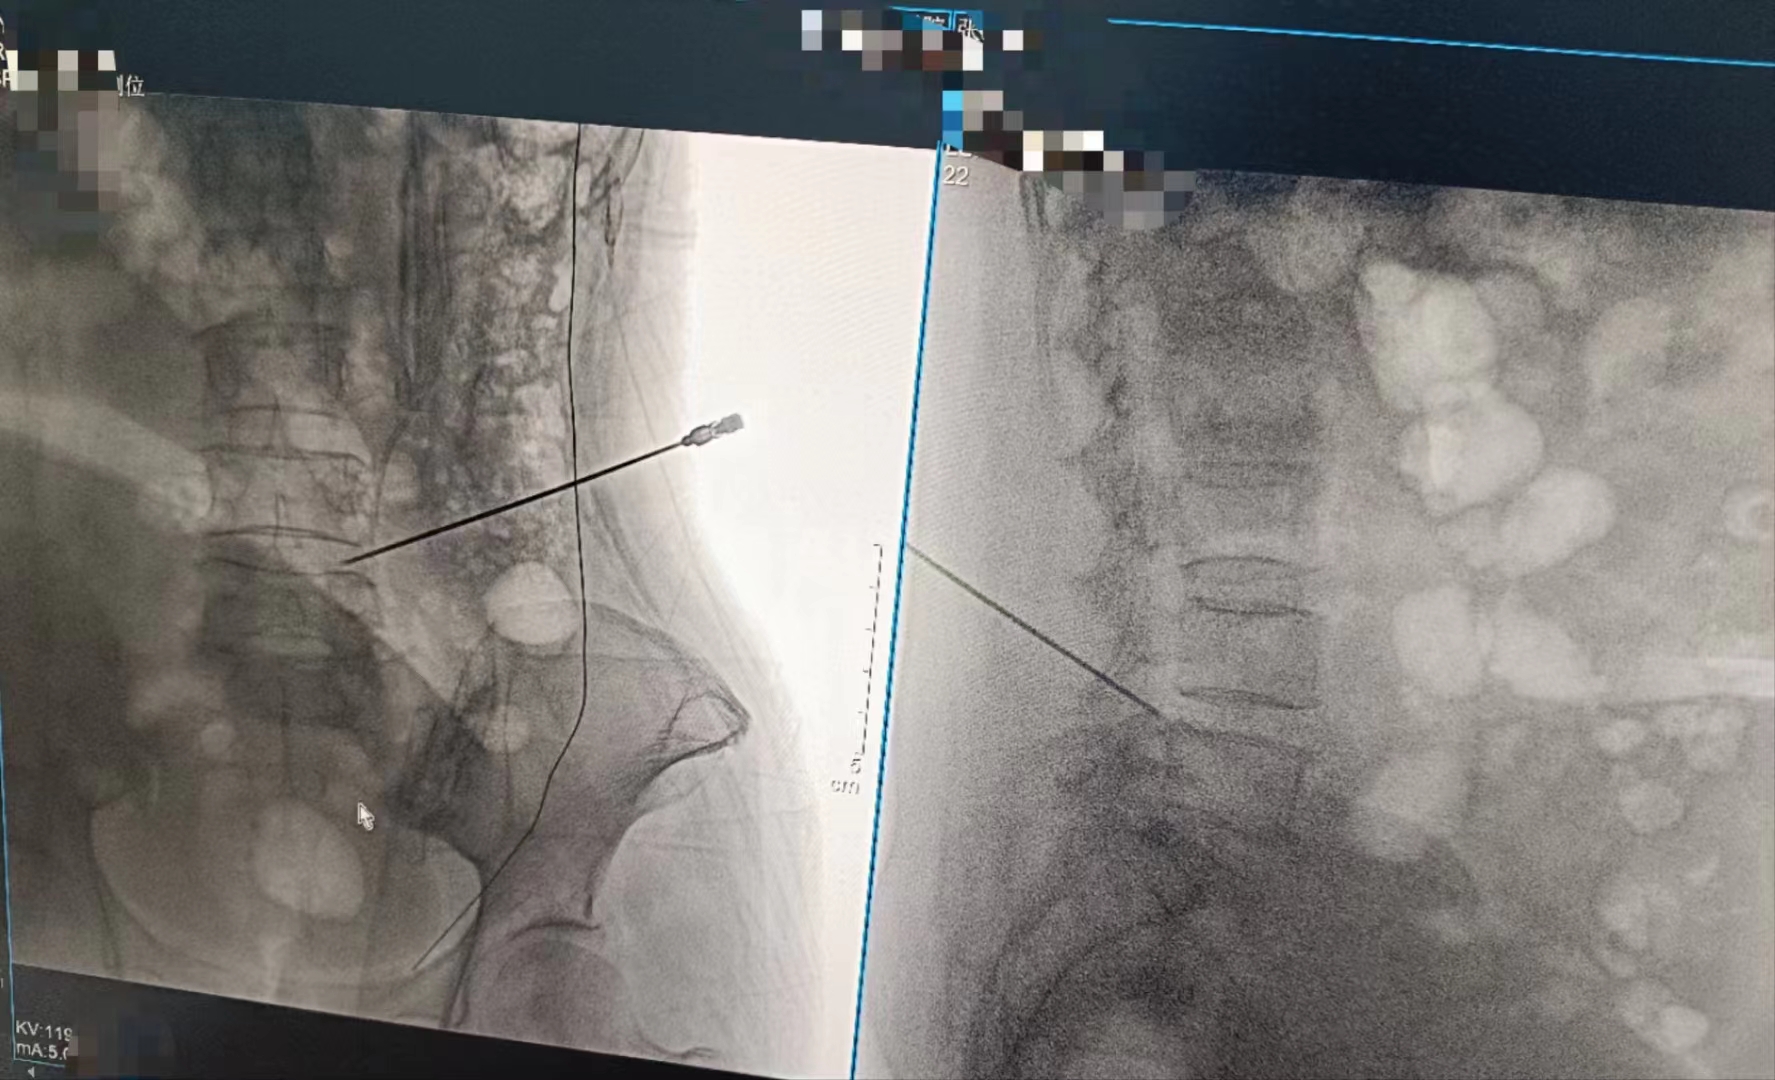

當設備啟動,那束柔和的X射線穿過患者的身體,捕捉下每一個細微的影像。那一刻,時間仿佛凝固,所有的目光都聚焦在那塊屏幕上。那里,生命的紋理清晰可見,疾病的陰影無處遁形。

手術順利完成,當醫(yī)生們露出疲憊而欣慰的笑容時,我知道,那不僅僅是勝利的喜悅,更是對生命的敬畏與珍視。而這一切,都離不開這臺數字化X射線攝影設備的默默付出。